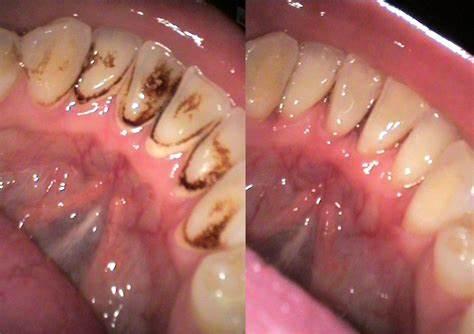

Scaling is a type of cleaning that uses a speci...